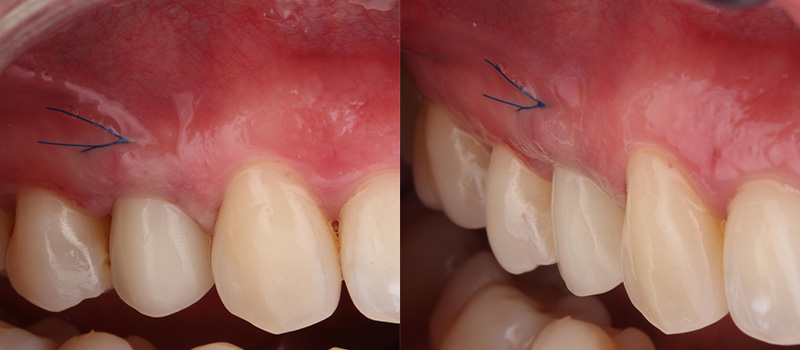

Fig. 05 : situation clinique à J10 (avant la dépose de la suture en 6.0 monofilament) vue latérale et vue vestibulaire.